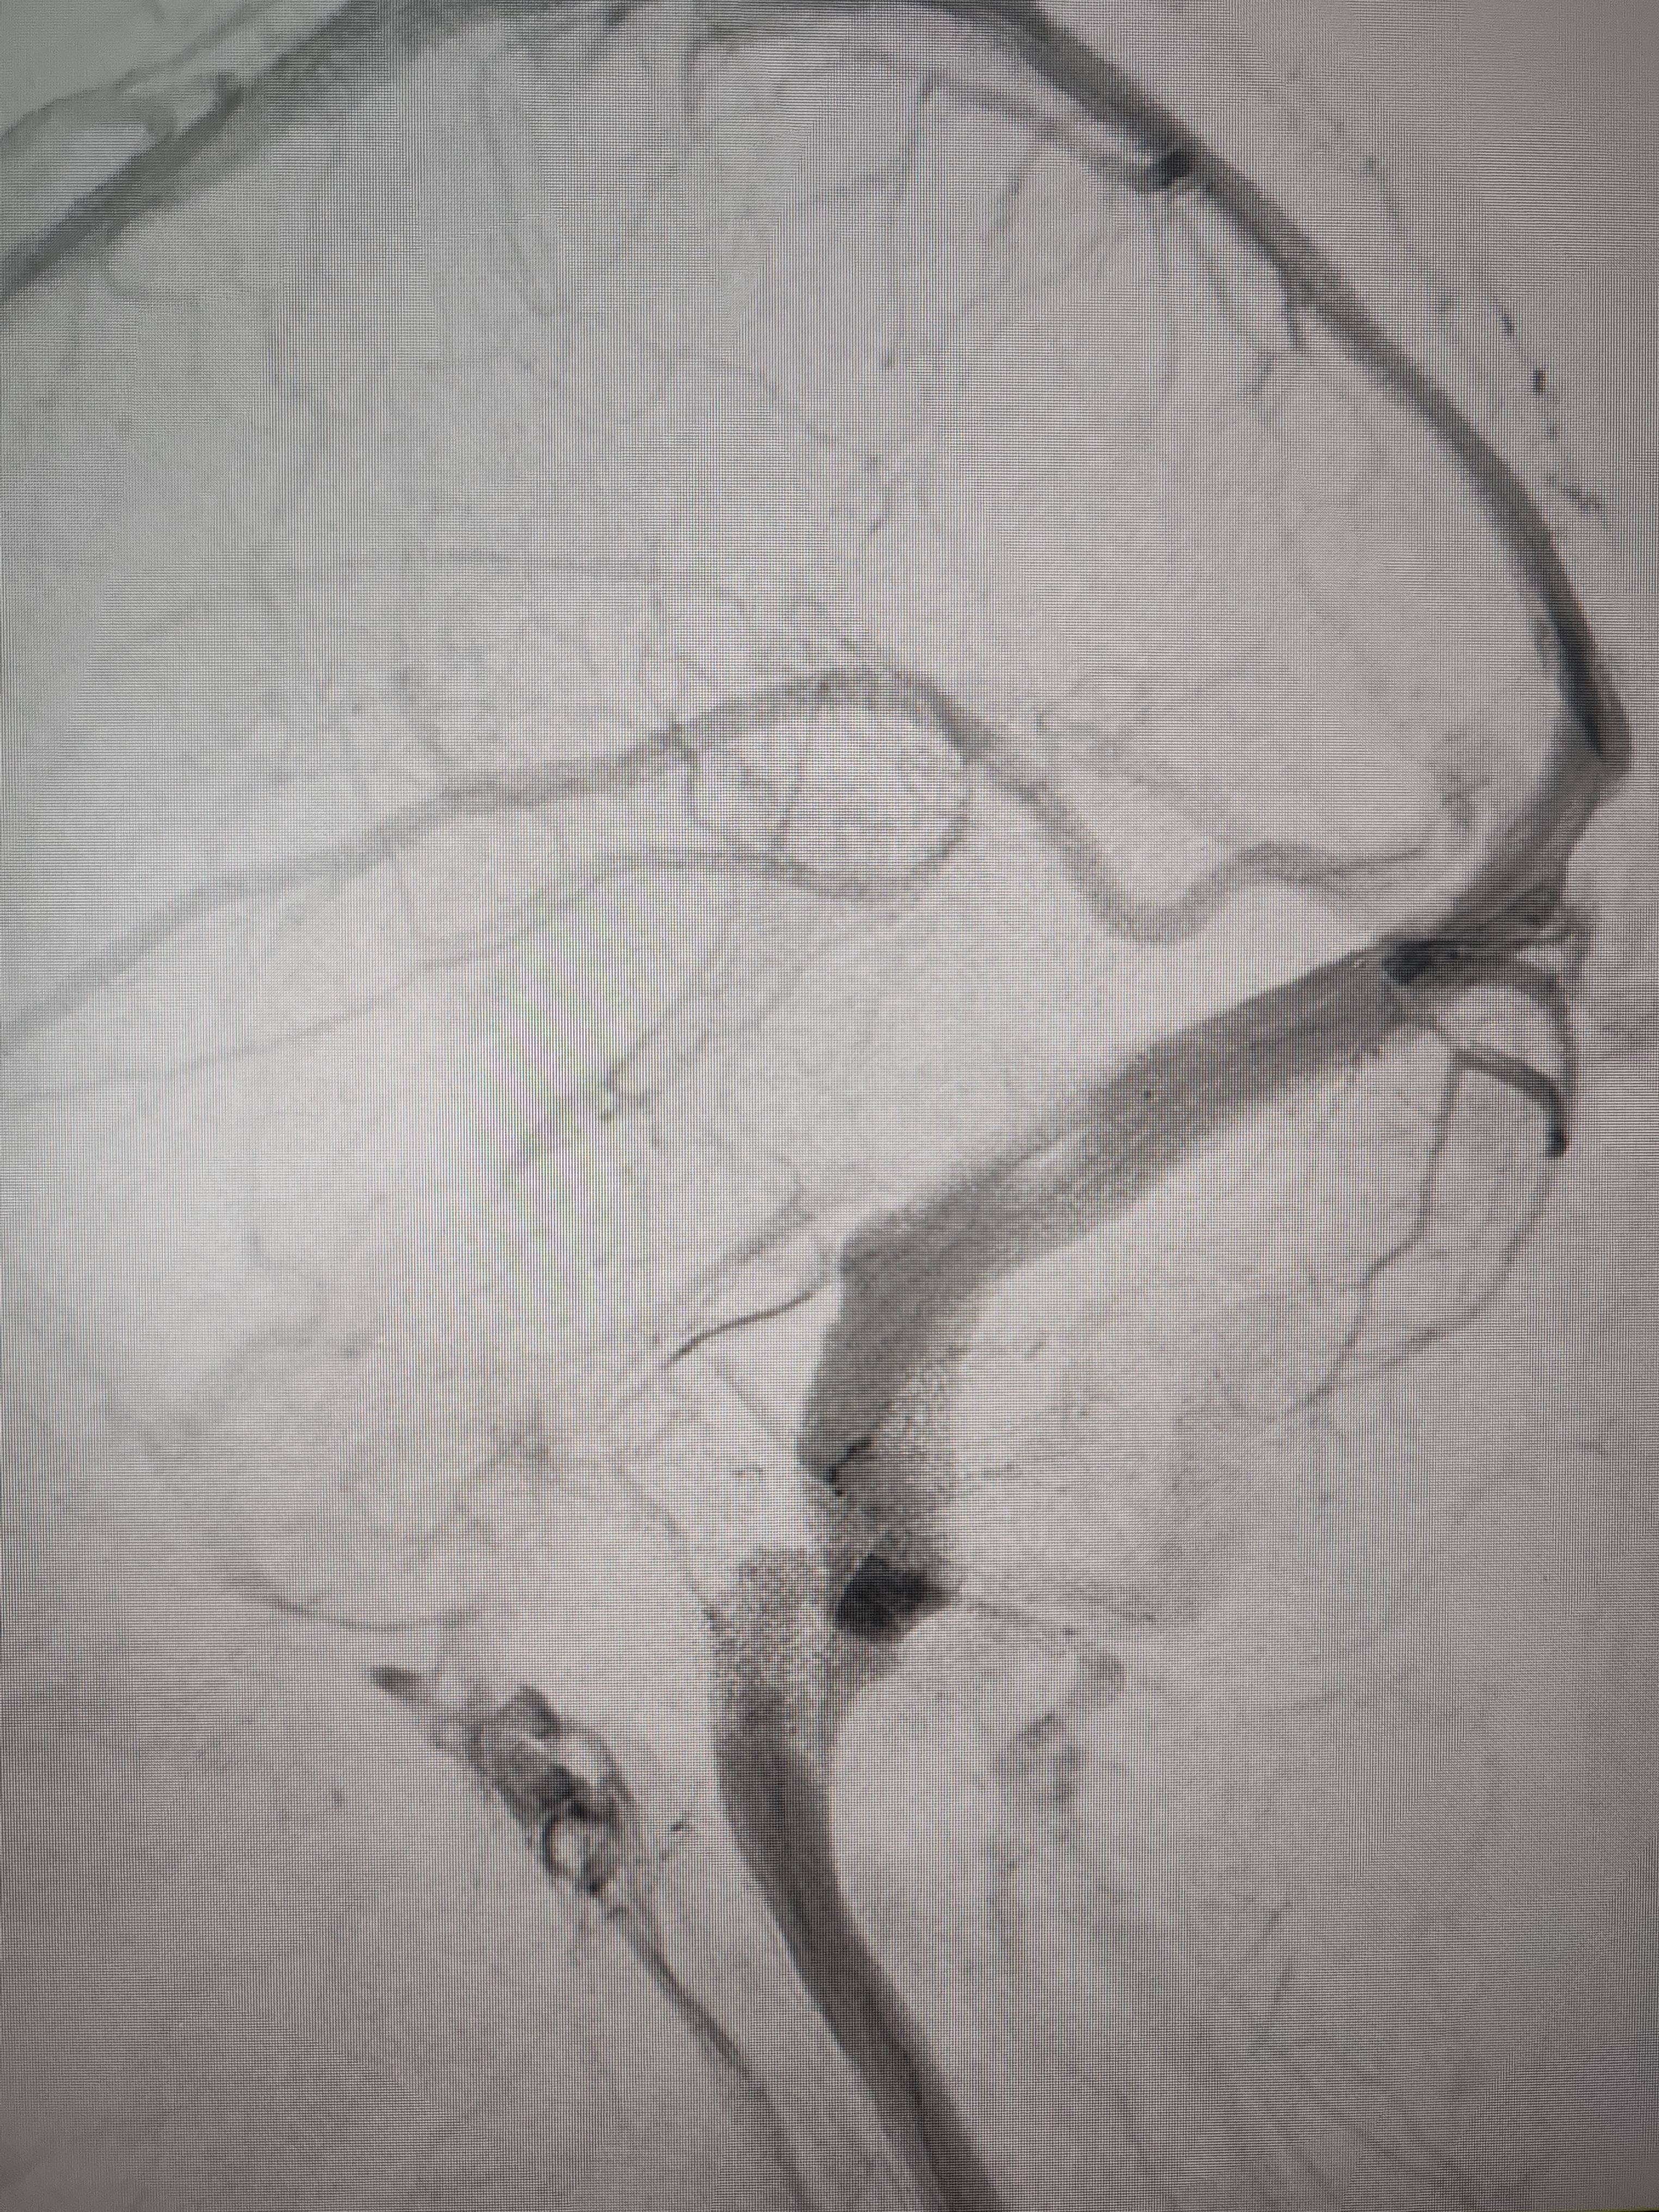

经过静脉窦支架置入手术治疗后,患者的静脉窦“堵点”被打通虚拟币交易技巧。 南方+ 欧阳少伟 拍摄

“从手术室出来,麻药清醒以后,我感觉整个世界都清静了,没想到效果这么立竿见影虚拟币交易技巧。”减轻病痛的赵女士,术后很是开心,次日就可下床自如活动,目前已康复出院。